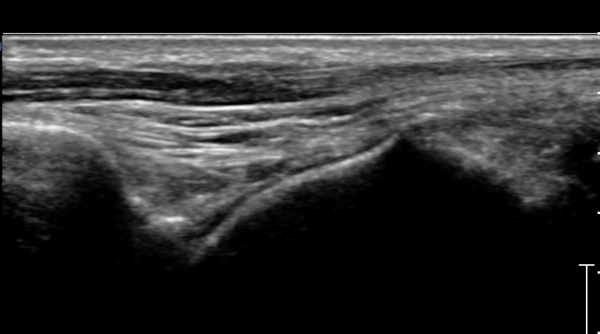

Á¾°ñºñ°ñÀδë Á¾´Ü¸é°Ë»ç¿¡¼­ °Å°ñÇϰüÀýÀÇ ¼ö¾×Àú·ù(Á¾°ñºñ°ñÀÎ´ë ½ÉºÎ ¼ö¾×Àú·ù)°¡

°üÂûµÈ´Ù(»çÁø 4).